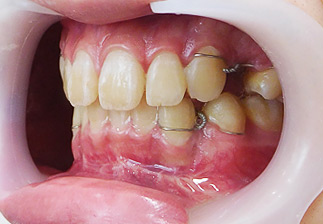

大阪府 19歳 男性

執刀医 辻和志

【治療内容】上下セットバック…上のアゴと下のアゴの両方が前に出ていた為、上下のアゴの骨を切って後ろに下げました。

【費用】上下セットバック 2,307,800円(税込)

【リスク】全身麻酔で行うため全身の健康状態が悪い方は行うことができません。また、手術当日は安静にしていただく必要があります。